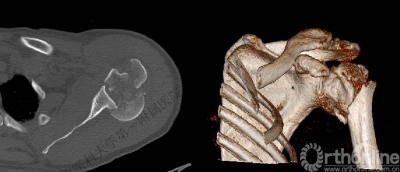

三、影像学

1.X线片

2.肩关节CT

确定肩关节后脱位。

了解反Hill-sachs损伤和程度。

观察肱骨近端主要骨折线和次要骨折线及形态。